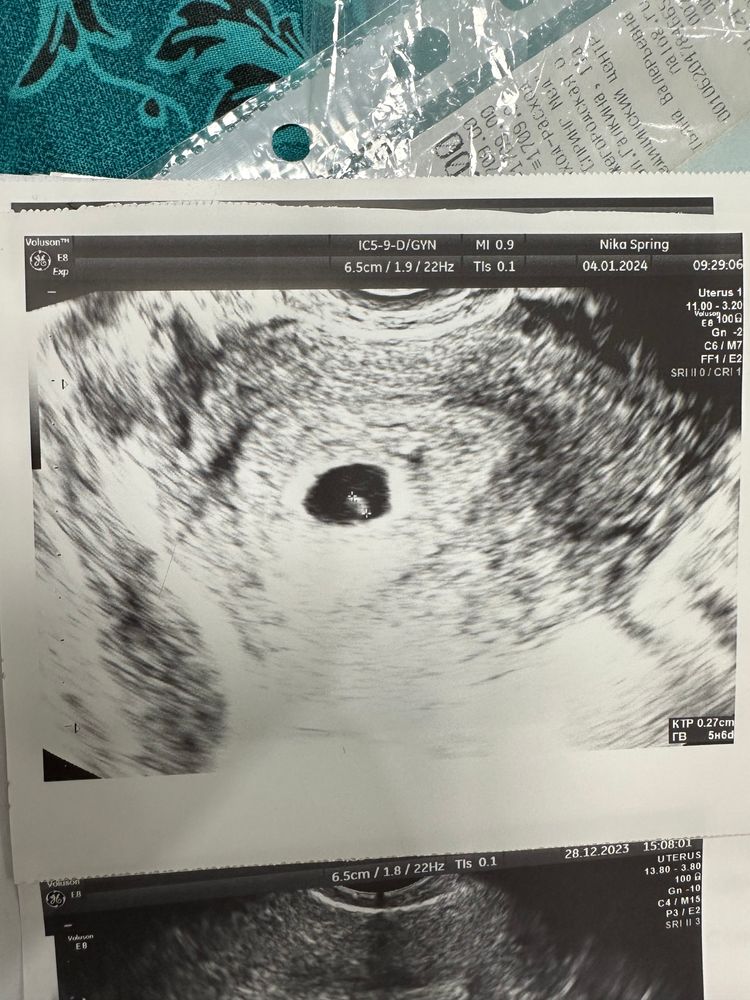

Душевные переживанияДевочки , поделитесь пожалуйста, была на узи почти 7 недель , сердце не слышно , но сказали возможно была поздняя овуляции и малыш развивается как надо , образуется 3 кольца , сказали подойти на 8 недели

Вы бы хоть размеры, которые Вам на узи намеряли написали бы. А то ничего не понятно, какой срок конкретно, какое ПЯ, ЖМ и КТР.

Алина, у вас ктр даже 3мм нет, подождите недельку, может подрастёт и все появится. Не торопитесь

Какой размер эмбриона. Если там уже больше 5мм и нет сердцебиения, то прогноз печальный.

Если КТР 1-3мм, то, возможно, поздняя овуляция и услышат через неделю.